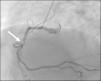

En cardiopatía isquémica: ¿es la elevación del segmento ST en cara anterior sinónimo de infarto agudo de miocardio anterior de ventrículo izquierdo?

In ischemic disease, is the anterior ST segment elevation a synonym for anterior left ventricular acute myocardial infarction?